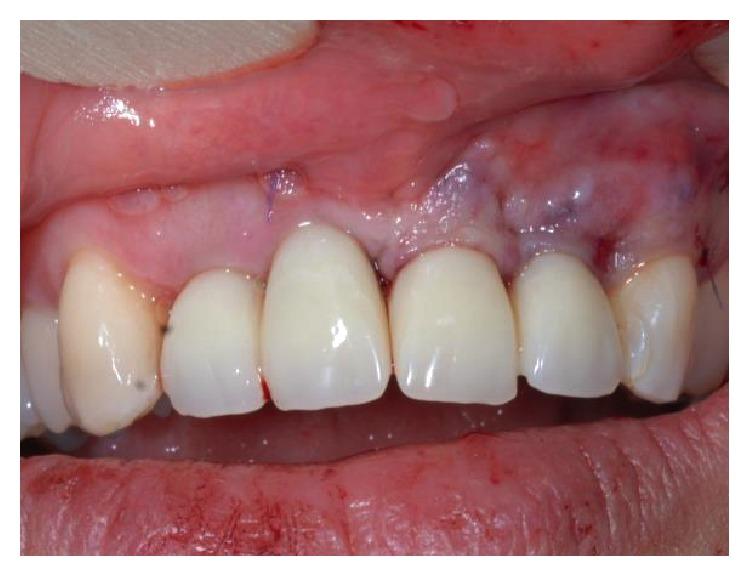

The functional and aesthetic restoration of teeth compromised due to aggressive periodontitis presents numerous challenges for the clinician. Horizontal bone loss and soft tissue destruction resulting from periodontitis can impede implant placement and the regeneration of an aesthetically pleasing gingival smile line, often requiring bone augmentation and mucogingival surgery, respectively. Conservative approaches to the treatment of aggressive periodontitis (i.e., treatments that use minimally invasive tools and techniques) have been purported to yield positive outcomes. Here, we report on the treatment and five-year follow-up of patient suffering from aggressive periodontitis using a minimally invasive surgical technique and implant system. By using the methods described herein, we were able to achieve the immediate aesthetic and functional restoration of the maxillary incisors in a case that would otherwise require bone augmentation and extensive mucogingival surgery. This technique represents a conservative and efficacious alternative to the aesthetic and functional replacement of teeth compromised due to aggressive periodontitis.

侵袭性牙周炎导致牙齿功能和美观受损,给临床医生带来诸多挑战。牙周炎引起的水平骨吸收和软组织破坏会妨碍种植体植入以及美观的牙龈微笑线的再生,通常分别需要进行骨增量和膜龈手术。据称,侵袭性牙周炎的保守治疗方法(即使用微创工具和技术的治疗方法)能产生积极效果。在此,我们报告了一名侵袭性牙周炎患者采用微创外科技术和种植系统的治疗及五年随访情况。通过使用本文所述方法,在原本需要骨增量和广泛膜龈手术的病例中,我们成功实现了上颌切牙的即刻美观和功能恢复。该技术是侵袭性牙周炎导致牙齿功能和美观受损时,一种保守且有效的替代治疗方法。